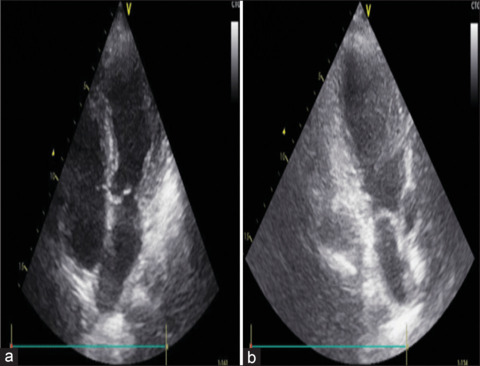

Takotsubo syndrome (TTS), also known as stress cardiomyopathy, is a life-threatening condition characterized by transient left ventricular dysfunction with nonischemic abnormalities. This syndrome in scenarios of anaphylactic shock is quite rare, with only a few cases reported. Early diagnosis and treatment are crucial. We presented a rare case of 58-year-old woman presented to our hospital due to an anaphylactic shock. The patient was stable and in the de-escalation dose of adrenaline (0.05 µg/kg/h). Twenty-two hours from exposure, the patient experienced pulmonary edema that required intubation, both adrenaline and dobutamine to maintain blood pressure. Echocardiography revealed a reduced ejection fraction of 35%. Subsequent coronary angiography showed no signs of coronary obstruction and left ventriculography provided typical apical ballooning and hyperkinesia in the basal region, highly suggesting TTS. The patient was successfully treated with inotrope and vasopressor and was discharged in stable condition after 7 days and improved normal heart function after 4 weeks. This case demonstrates the delayed onset of adrenaline-induced takotsubo complicated with pulmonary edema in a patient with anaphylactic shock due to antibiotics despite a de-escalation dose of adrenaline. Regardless of the duration of the event or the optimal epinephrine dosage in patients with anaphylactic shock, physicians should be aware of the risk of TTS.

Takotsubo综合征(TTS),也被称为应激性心肌病,是一种危及生命的疾病,其特征是短暂性左心室功能障碍伴非缺血性异常。在过敏性休克的情况下,这种综合征是相当罕见的,只有少数病例报道。早期诊断和治疗至关重要。我们提出一个罕见的病例58岁的妇女提出了我们的医院由于过敏性休克。患者病情稳定,肾上腺素降剂量(0.05µg/kg/h)。暴露22小时后,患者出现肺水肿,需要插管,肾上腺素和多巴酚丁胺来维持血压。超声心动图显示射血分数降低35%。随后的冠状动脉造影未见冠状动脉阻塞迹象,左心室造影显示典型的根尖球囊和基底区运动亢进,高度提示TTS。患者经肌力和血管加压药治疗成功,7天后出院,病情稳定,4周后心功能恢复正常。本病例显示了延迟发作的肾上腺素诱导的takotsubo并发肺水肿患者,尽管肾上腺素剂量降低,但抗生素引起的过敏性休克。无论过敏性休克患者的事件持续时间或最佳肾上腺素剂量如何,医生都应该意识到TTS的风险。